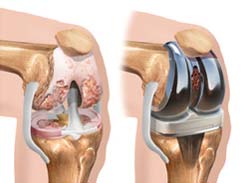

اگر بخواهیم به صورت کامل تعویض مفصل زانو را انجام دهیم باید انتهای استخوانهای مفصل زانو (استخوان درشت نی) و استخوان ران (فمور) برداشته شود و بخشهای مصنوعی جایگزین آن گردد. بخشهای جایگزین شده از کاسهای فلزی و پلاستیکی تشکیل میشود که هر یک به ترتیب روی انتهای استخوان ران و سر استخوان درشت نی قرار میگیرد. پروتز پلاستیکی نیز گاهی اوقات در تعویض کاسه زانو مورد استفاده قرار میگیرد.